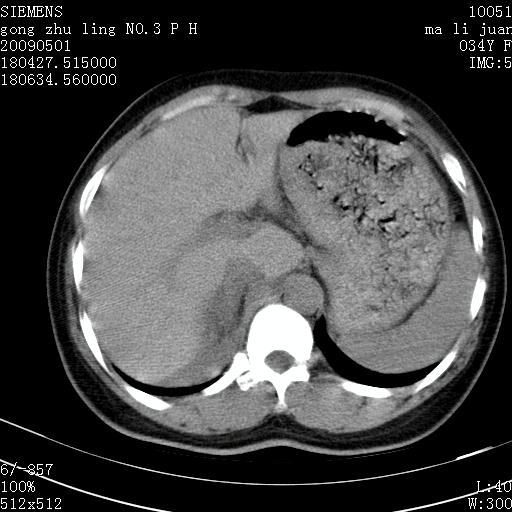

标题: CT19733:右肾碎裂

青年女性,骑摩托车摔伤。

右肾碎裂伤,包膜下血肿。

术中仅见右肾碎裂,肾蒂血管未见断裂。